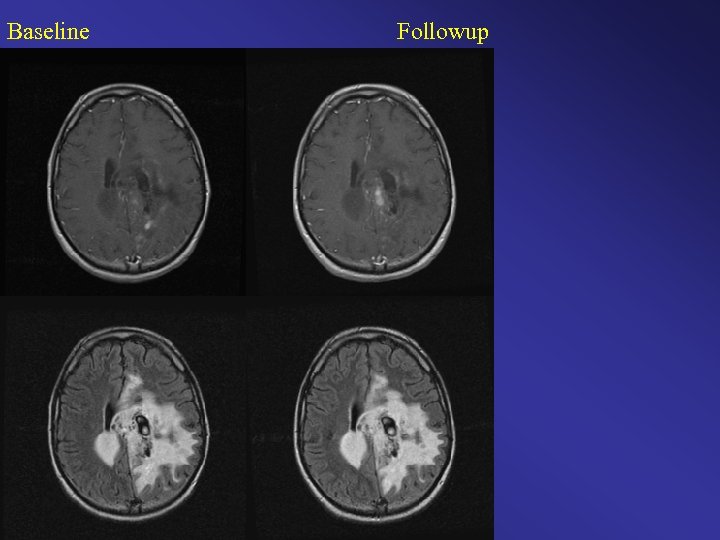

Baseline Followup

Baseline Followup Change or No Change?